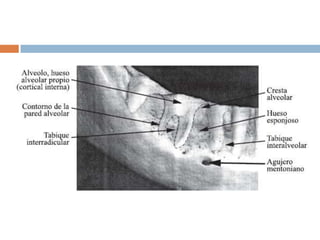

El proceso alveolar consiste en:Tabla externa de hueso cortical  hueso haversiano y laminillas óseas compactadas.Pared interna del alveolo  hueso compacto delgado “hueso alveolar” y en rx aparece como cortical alveolar.Tuberculas esponjosas  2 capas compactas q son el soporte del hueso alveolar.El tabique interdental  hueso esponjoso – soporte rodeado.Hueso basal  mandíbula que esta en sentido apical, pero no tiene relación con los dientes.Vestibular y lingual de los alveolos  hueso compacto solo y el Esponjoso  rodea la cortical alveolar en zona apical.

Tabique interdentalEs hueso esponjoso limitado por las corticales alveolares de la pared del alveolo de los dientes vecinos.

Topografía ósea.El contorno de hueso es según a la prominencia de las raíces.Cada persona es diferente en la Alineación de los dientes, la angulacion de la raíz con el hueso y las fuerzas oclusivas…Afectando la altura y espesor de las tablas Oseas vestibulares y linguales.